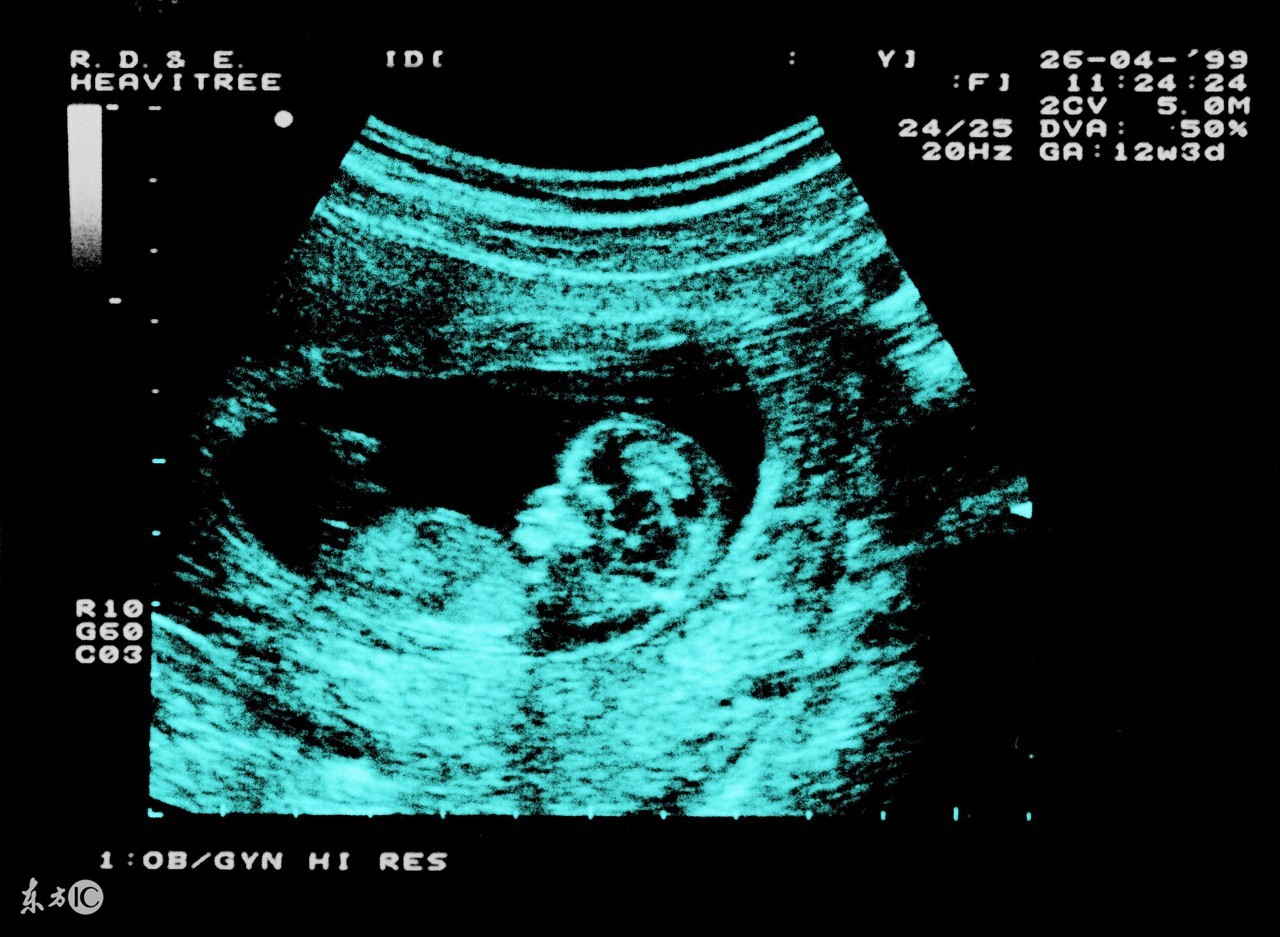

妊娠28周后经腹部、阴道、B超检查可检查是否为异常胎位。妊娠28周以前,因为羊水相对较多,胎宝宝又比较小,在子宫内活动范围较大,所以位置不容易固定。妊娠32周以后,宝宝生长迅速,羊水相对减少,此时胎宝宝的姿势和位置相对固定。所以在孕32周以后,如果宝宝还是“胎位不正”就基本上等于确定了,当然也不排除极少数胎宝宝来个“意外之举”。所以胎位不正最合适的纠正时间为孕30-32周之间。